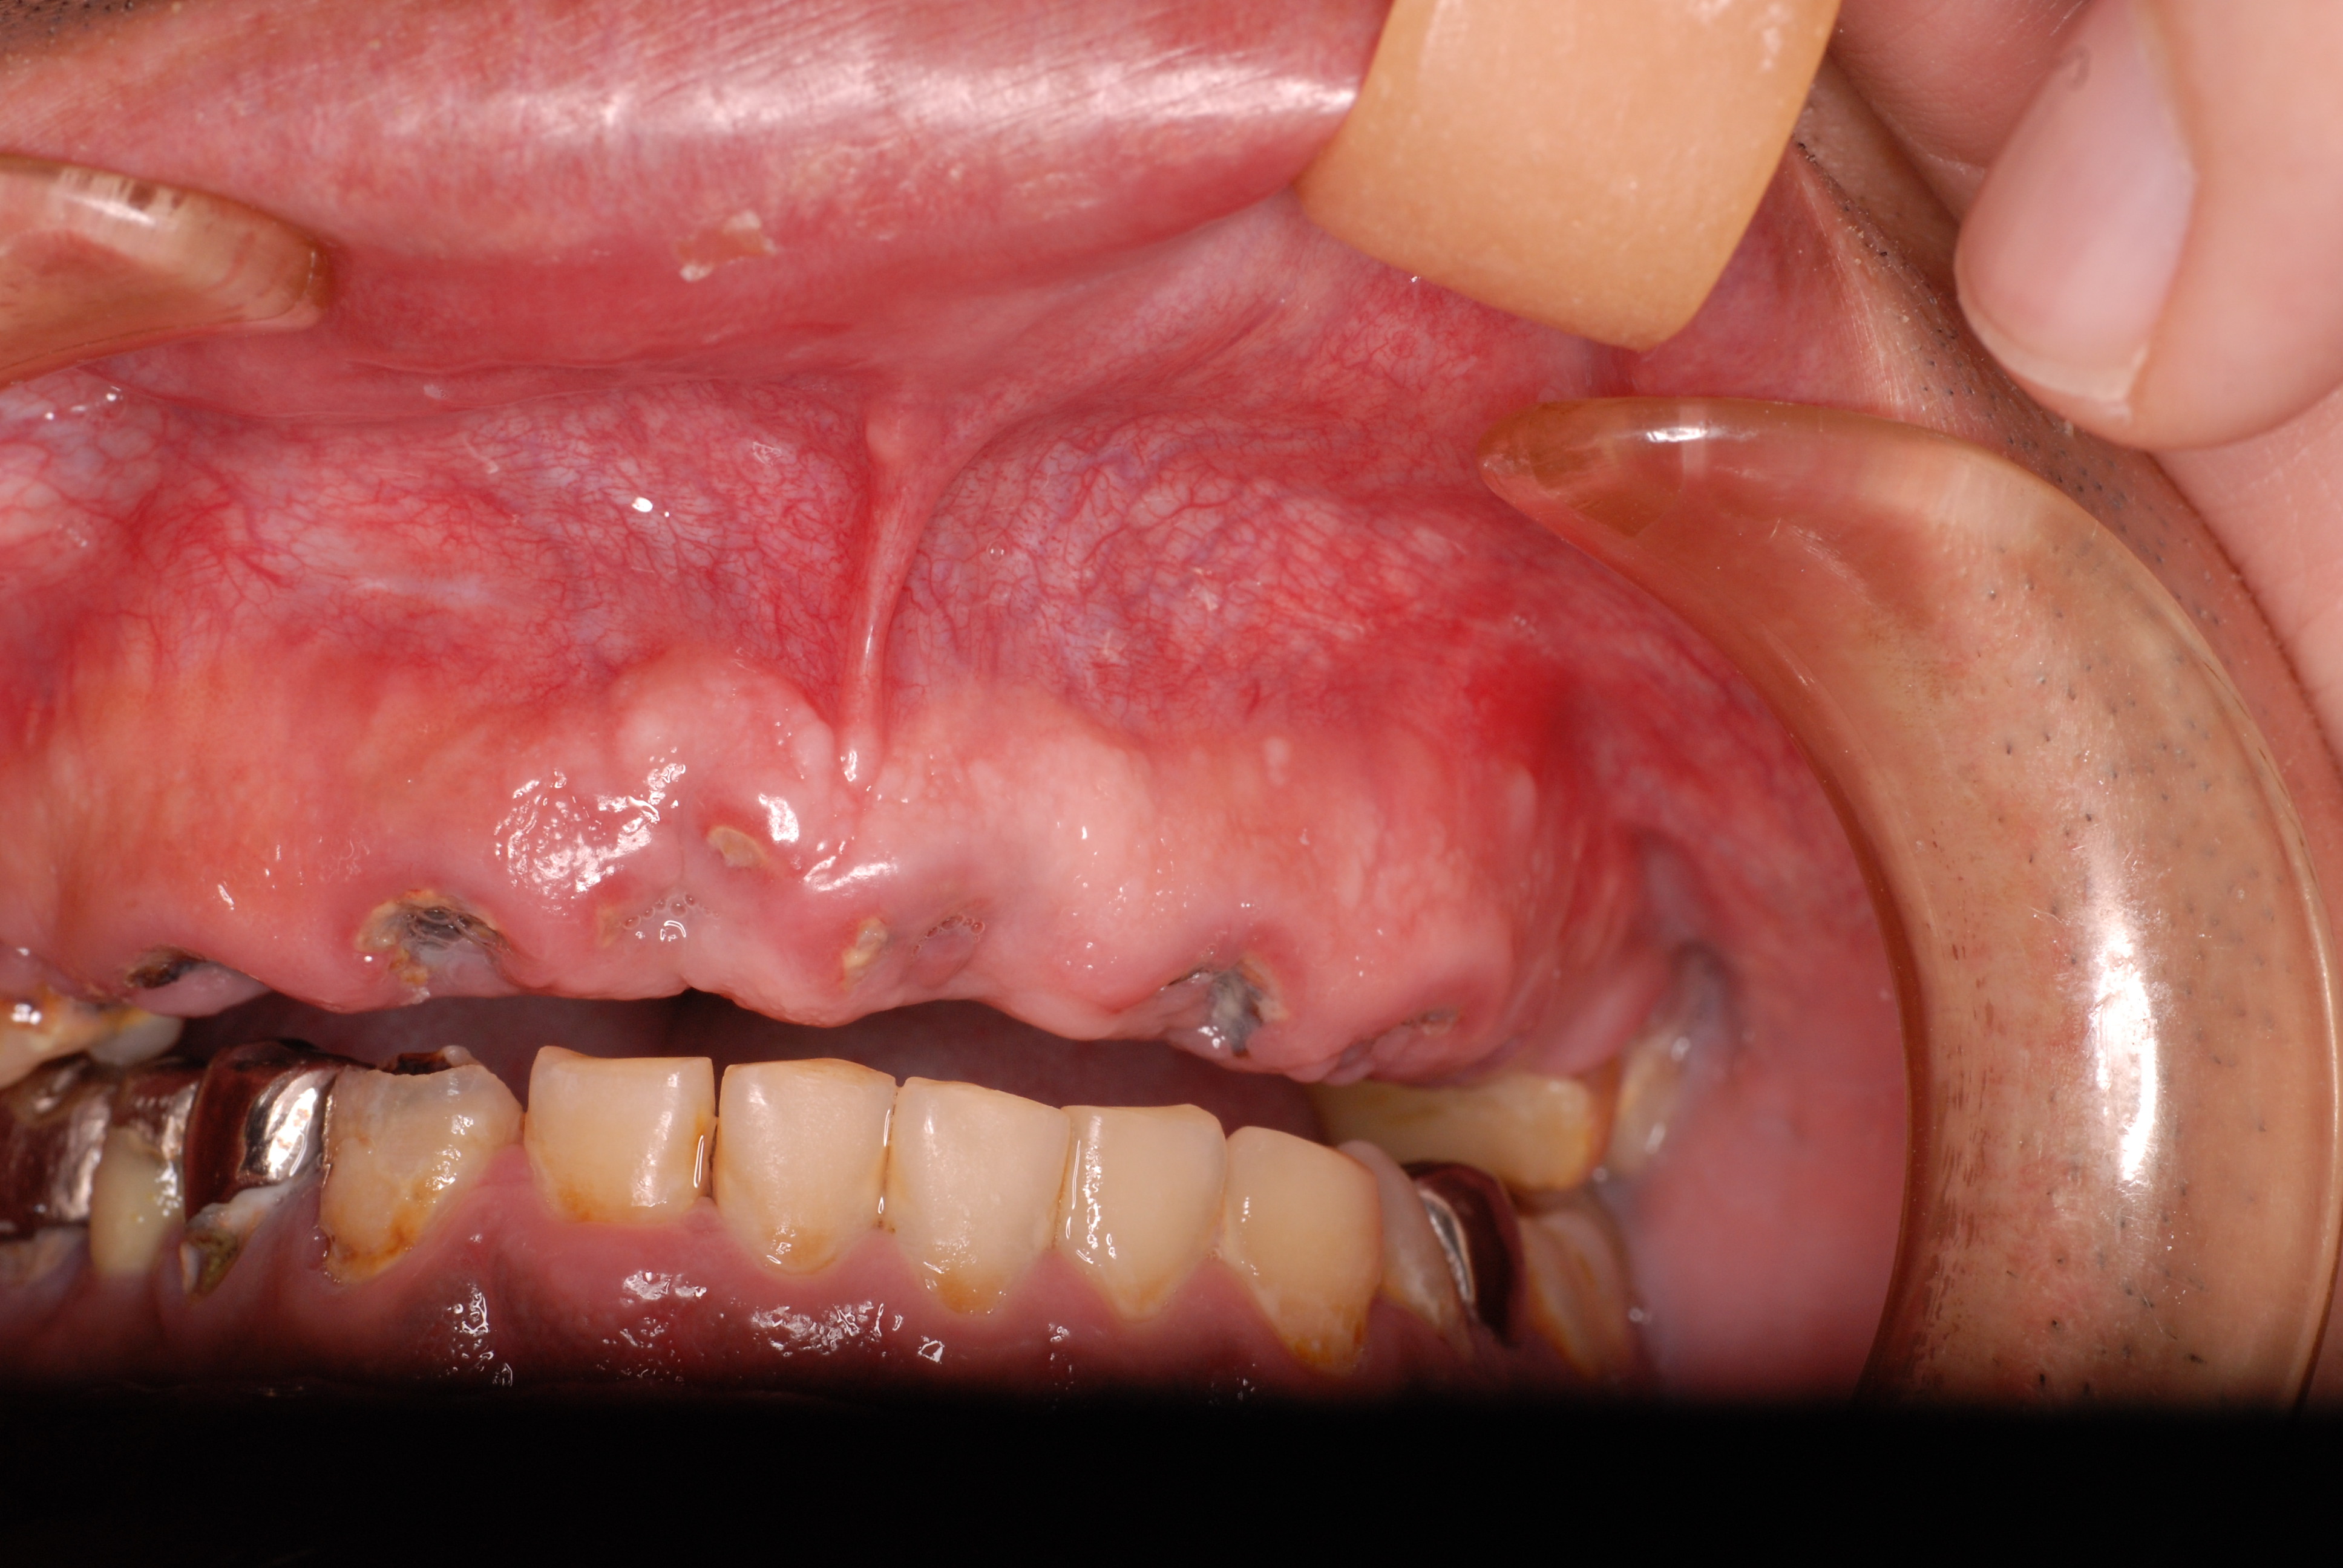

歯無しにならない長い話し

今回約1年近くかかった方のとりあえずの治療が終了しました。

でも、歯医者がどんなに何かを被せても元の健康な状態になった訳ではないのです。歯医者さんは、何かを詰めたり被せたりしますけれど、これは、修復でありお口の中に何か造作をしたに過ぎません。

磨かなければ、磨けなければすべて崩壊して入れ歯、或いは人工歯根へまっしぐらなんです。

お口の中の病気は基本的には、虫歯、歯周病、そして神経の処置以外にはあまりないのです。ですからばい菌で悪くなる訳ですからばい菌を毎日毎日取り除く以外に崩れていくのを止める方法はないのです。

ブラシの使い方に習熟しましょう。

最初の状態です。若いのにすぐ外れる入れ歯をいれていらっしゃいました。

DSC_0167DSC_0162

DSC_0166DSC_0165

DSC_0164

そしてひとまず終了した状態です。

DSC_0018DSC_0023

DSC_0027

このように綺麗になりましたが元の健康な状態になったのではないのです。ばい菌が歯の周りから採れていなければ元の木阿弥。

おそらく差し歯にもできず入れ歯かインプラントという人工歯根になる事でしょう。いやはやいくら費用がかかるのやら患者さんのことながらため息が出ます。

歯医者では病気を治していないことが多いのです。ただ詰めたり被せたりしているのに過ぎません。注意しないともっとひどいことになります。

そして、虫歯や歯周病、そして神経の処置は医療行為ですから誰でも100%うまくいくかというと、うまくいっていないことが多いのです。医療行為は難しいのです。良い歯の医者に当たる事を祈ります。

歯に何かを被せることは医者のやることではなくお口の大工さんがやることなのです。ですから歯医者は、大工と医者を同時にやっていることになりますね。

歯医者から口腔科の医師へ脱皮しなければなりません。日々精進あるのみ!